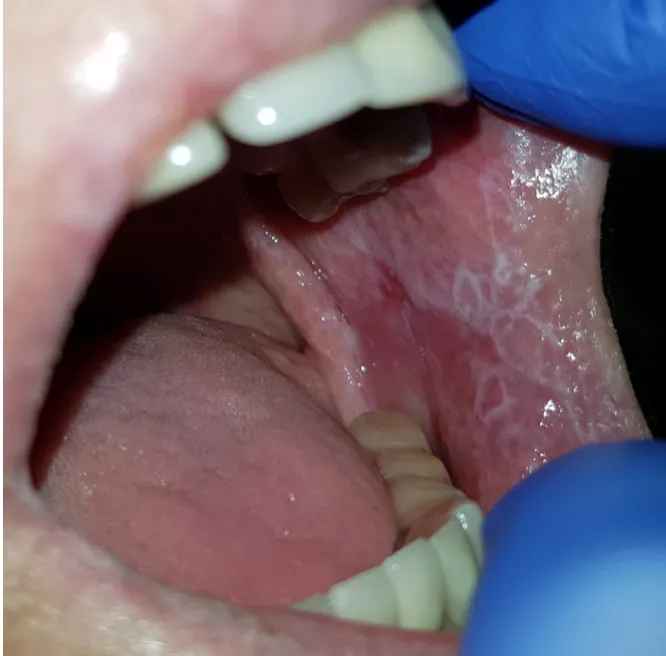

Najbardziej charakterystycznym objawem liszaja płaskiego w jamie ustnej jest tzw. siateczka Wickhama. To białe, koronkowe lub drzewkowate linie, które najczęściej pojawiają się na wewnętrznej stronie policzków, ale mogą również występować na języku, dziąsłach czy podniebieniu. Poza tym pacjenci często skarżą się na pieczenie, ból, a także suchość w ustach. W zależności od wyglądu i nasilenia zmian wyróżniamy kilka postaci klinicznych OLP:

- Postać siatkowata: Jest to najczęstsza forma, charakteryzująca się wspomnianą siateczką Wickhama. Często jest bezbolesna i może być wykryta przypadkowo podczas rutynowej wizyty u stomatologa.

- Postać nadżerkowa (wrzodziejąca): Ta forma jest znacznie bardziej uciążliwa i bolesna. Charakteryzuje się trudno gojącymi się owrzodzeniami i nadżerkami, które mogą powodować znaczny dyskomfort podczas jedzenia i mówienia.

- Postać zanikowa: Objawia się czerwonymi, gładkimi plamami, często połączonymi z nadwrażliwością na temperaturę czy smaki. Może współistnieć z postacią nadżerkową.